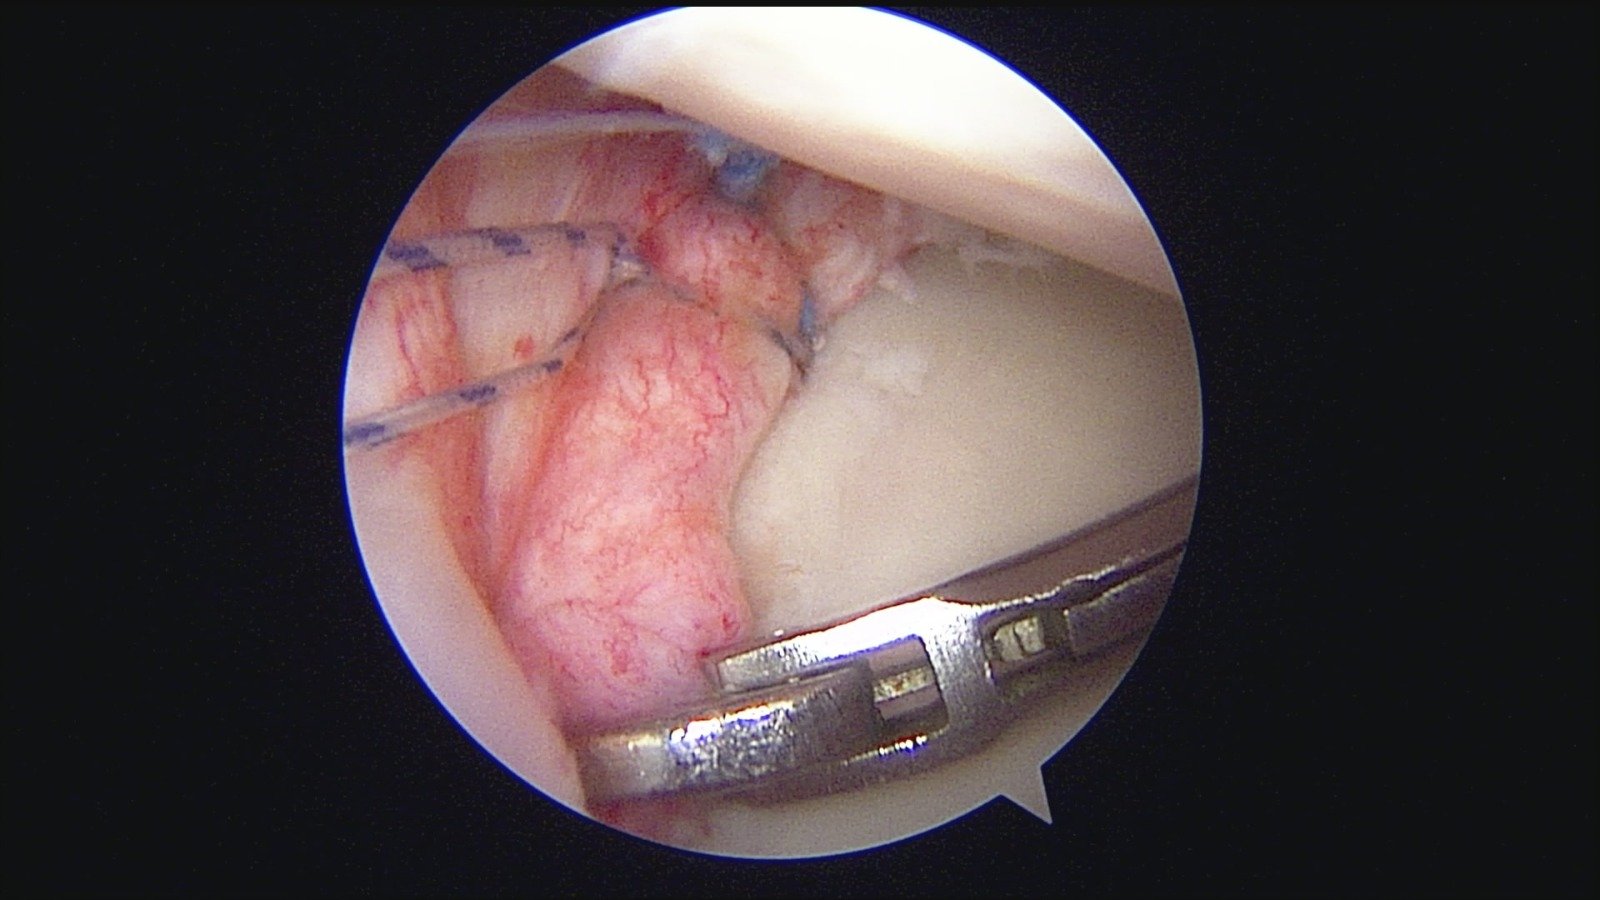

GalleryShoulder rotator cuff repair Meniscus root repair Meniscus repair Bankart repair for recurrent shoulder dislocation ACL reconstruction Machines Instruments